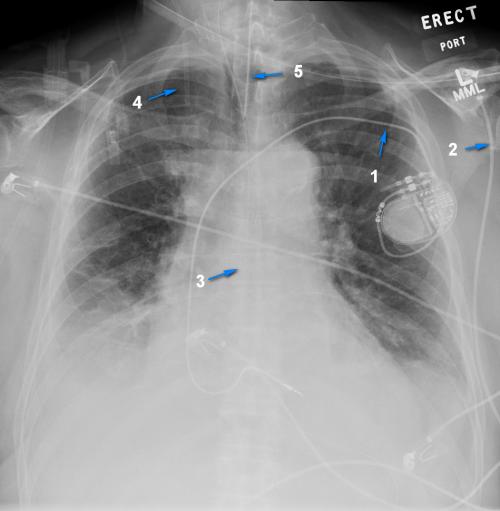

Match the following tubes, lines, and devices with the highlighted structures on the X-ray.

Choose all that apply

1 is a cardiac pacemaker

2 is a CVP

3 is a NG tube

4 is an ETT tube

5 is an EKG lead